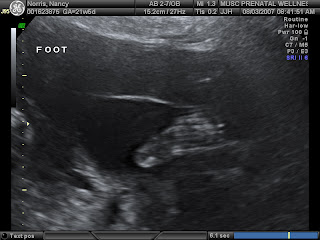

In the middle of the screen, you can see a picture of her little foot

We are officially 22 weeks and 1 day pregnant today. And we FINALLY have confirmation that the Jelly Bean is a GIRL! We also have confirmation that our little girl is S-T-U-B-B-O-R-N! We went to MUSC on Friday for our level 2 ultrasound.

If you recall, we were sent to MUSC because the baby was in a position that made it difficult for our local sonographer to capture a clear view of her heart and her nose and lips. Well...she was still in that position on Friday, and she has no interest whatsoever in changing positions.

The sonographer at MUSC was able to capture a picture of her little lips and nose, but neither she nor her supervisor were able to capture the 5 pictures they needed of her heart. The heart seemed to be just fine, and it appeared to be beating normally, but the girls couldn't get the pictures they needed. We were there for an hour and a half -- I drank juice, I ate ice, I walked around, I jumped around, I pushed on my belly, I rolled from one side to the other, but we could not get her to budge. She is obviously in a very cozy spot and does not care to move. So...we go back on August 22 for one more try.